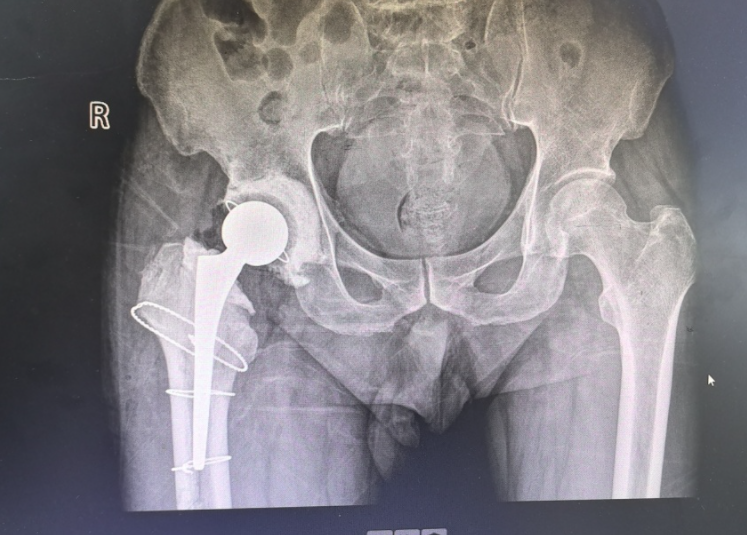

两年前,患者张先生确诊了股骨头坏死,随着疼痛逐渐加剧,他在当地医院接受了右侧全髋关节置换手术。

第一期取出感染假体,置入临时性带抗生素的骨水泥型髋关节假体,进行抗感染治疗,不仅能有效预防肌肉萎缩、骨质疏松等并发症,还能使患者在术后逐渐恢复行走能力。

待控制感染后,再进行第二期手术,取出临时假体,再次置入人工髋关节,手术治疗才算彻底完成。

并安装了骨水泥型假体

第一期术后

第一期手术术后